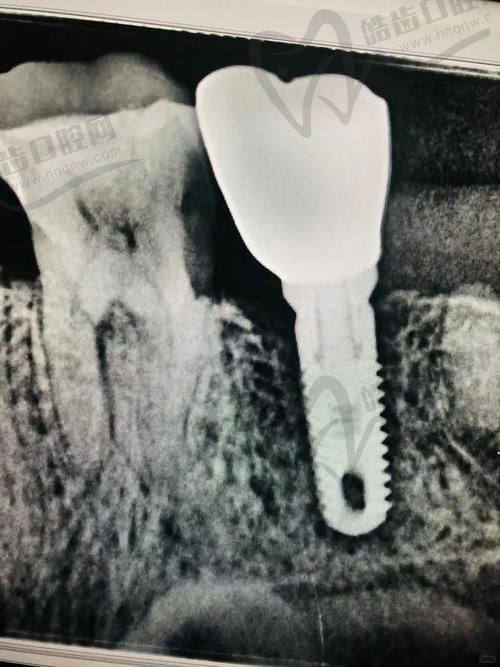

技术优势:医院拥有精良的口腔诊疗设备,如口腔显微镜、数字化口腔扫描仪等,为种植手术提供精细的诊断和治疗。医生团队由多名经验多的口腔骨干医生组成,他们在种植满口牙方面有着丰富的临床经验和独特的技术优势。采用精良的种植技术,如即刻种植、all-on-4种植等,缩短患者的治疗周期,提高患者的生活质量。